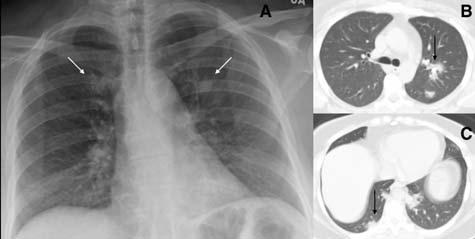

Fig 6 — Serial CXR’s of a patient with COVID-19 showing development of atypical findings during the admission. The admission radiograph (A) demonstrates multifocal peripheral opacities (white arrow), followed by the development of right pneumothorax (black arrow) on day 7 (B) of admission with improvement in parenchymal changes subsequently on day 15 of admission (C). He developed extensive left pneumothorax (black arrow) and surgical emphysema (star)(D)of the chest wall later in the course. Images courtesy of Dr Amrita Bajaj, Glenfield Hospital, Leicester.

Fig 7 — Atypical presentation of COVID-19 in the form of nodules (arrows) seen on the CXR (A) and the corresponding CT (B). Image reproduced with permission from Covid-19 Database of the Fleischner Society.